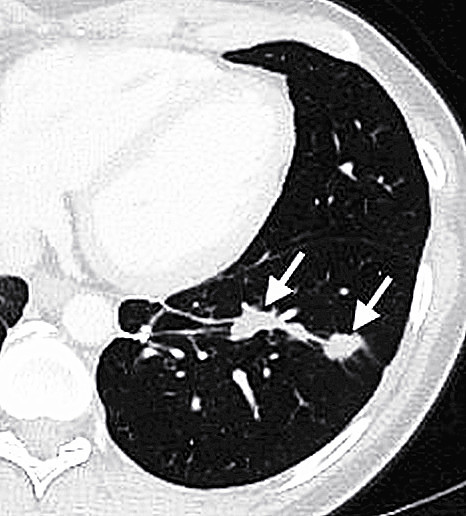

美國癌症中心研究人員分離出膽管癌患者體內一種稱為腫瘤滲透淋巴細胞(TIL)的白血球,此淋巴球能辨識患者癌細胞上突變的「ERBB2IP」蛋白質;研究人員每次將4百多億顆TIL輸回患者體內,其中能辨識ERBB2IP的TIL約占4分之一,成功使患者蔓延至肺與肝的癌細胞停止擴散,而當能辨識ERBB2IP的TIL比例提高到95%時,腫瘤體積也不斷縮小。